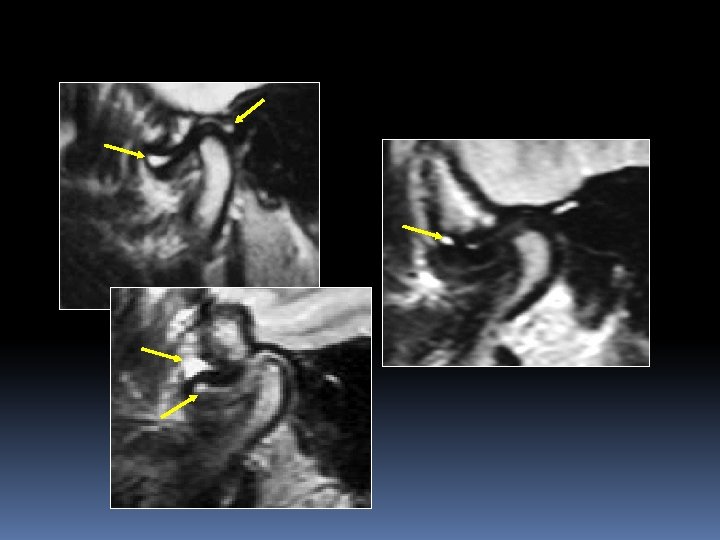

Dynamique discocondylienne Bouche fermée Bouche ouverte

Limitation de la course condylienne Immobilité condylienne hyperlaxité condylienne

Subluxation discale antérieure réductible Déplacement discal antérieur léger Disque reprend sa place à l’ouverture buccale

Luxation antéro-interne réductible Déplacement discal antérieur et interne Disque en place à l’ouverture buccal Bouche ouverte Bouche fermée

Luxation antérieure irréductible Déplacement antérieur du disque plicaturé Propulsion condylienne limitée, le disque reste en avant du condyle

Luxation antéro-externe réductible n Déplacement antérieur et externe du disque applati n Propulsion condylienne normale, le disque est en position normale

Luxation antéro-externe irréductible Disque plicaturé La course condylienne est normale

Détermination de la hauteur de recaptation discale : semi ouverture buccale sur cale Déplacement antérieur du disque Semi ouverture Le disque se replace à l’aplomb du condyle. En fin d’ouverture, la position discocondylienne est normale. La hauteur de recaptation correspond à la hauteur d’ouverture permettant le repositionnement discal.